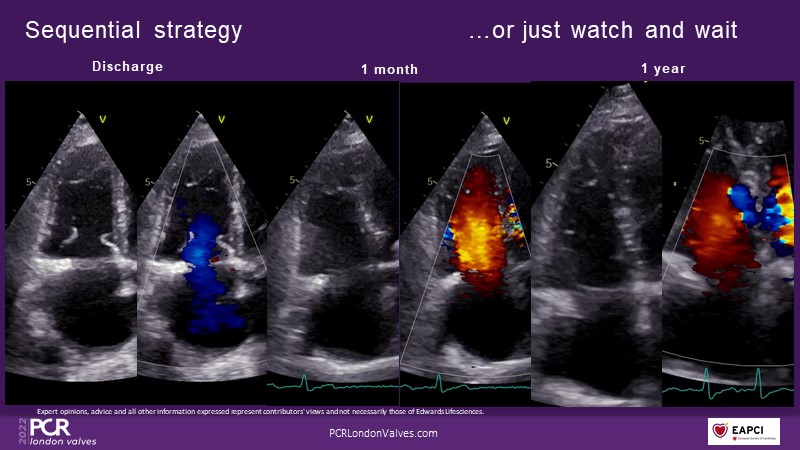

This innovative session takes you through the patient selection and anatomical characteristics when selecting amongst the different transcatheter options to treat tricuspid regurgitation, followed by a recorded demonstration using the PASCAL Precision repair system.